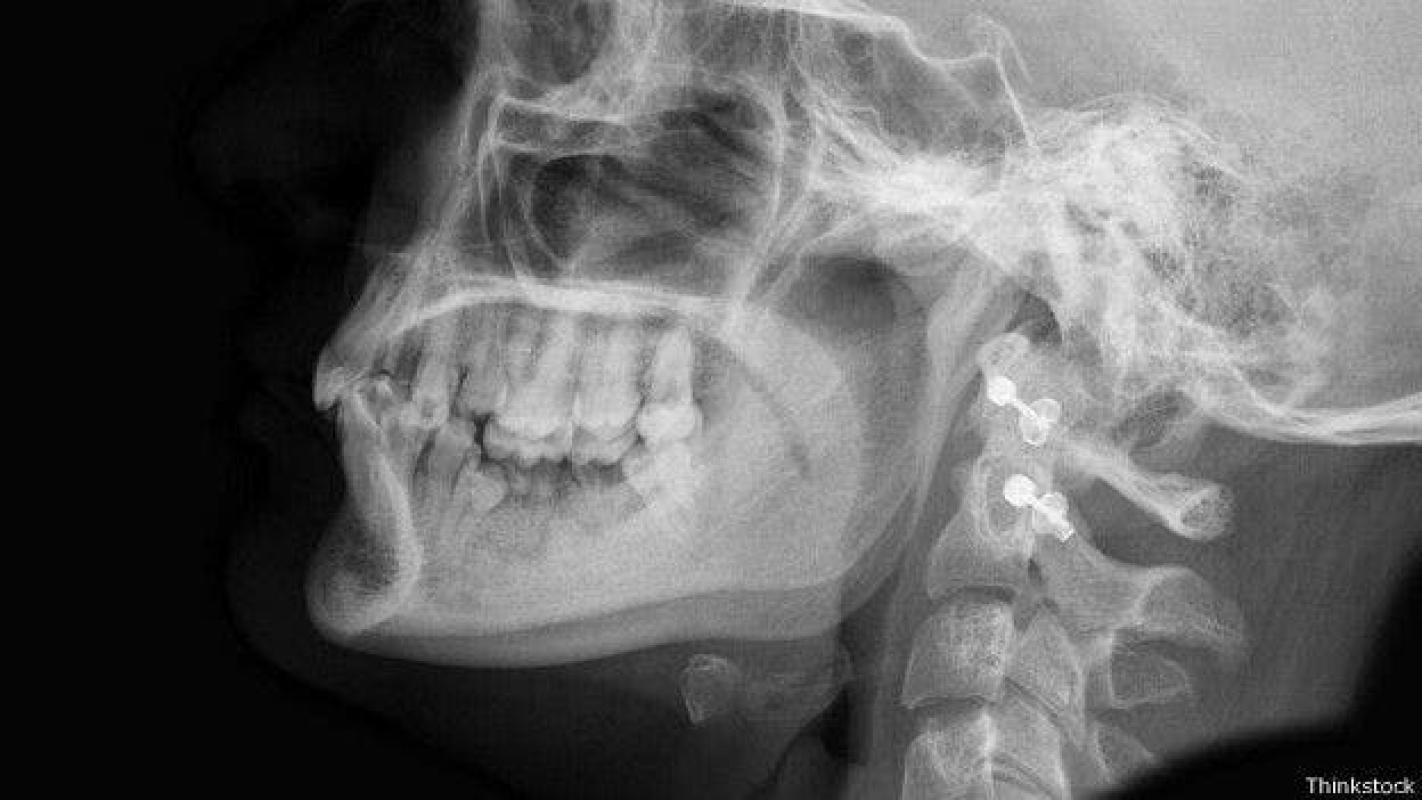

Un joven de 15 años, de la ciudad de Hangzhou, en China, sufrió una extraña condición luego de aguantar un dolor de muelas durantes un año. Cuando se decidió a visitar al doctor le descubrieron un tumor conocido como ameloblastoma, el cual le había causado un enorme "agujero" en la mandíbula.

Una tomografía 3D reveló el daño causado por el tumor, que ya le había desgastado la mitad el mandibula inferior, evidenciando otras lesiones menores.

El joven tuvo que ser sometido a una cirugía que duró tres horas, para poder recuperar la mandíbula dañada y extraer el tumor. Los médicos esperan que los implantes dentales le devuelvan la funcionalidad maxilar